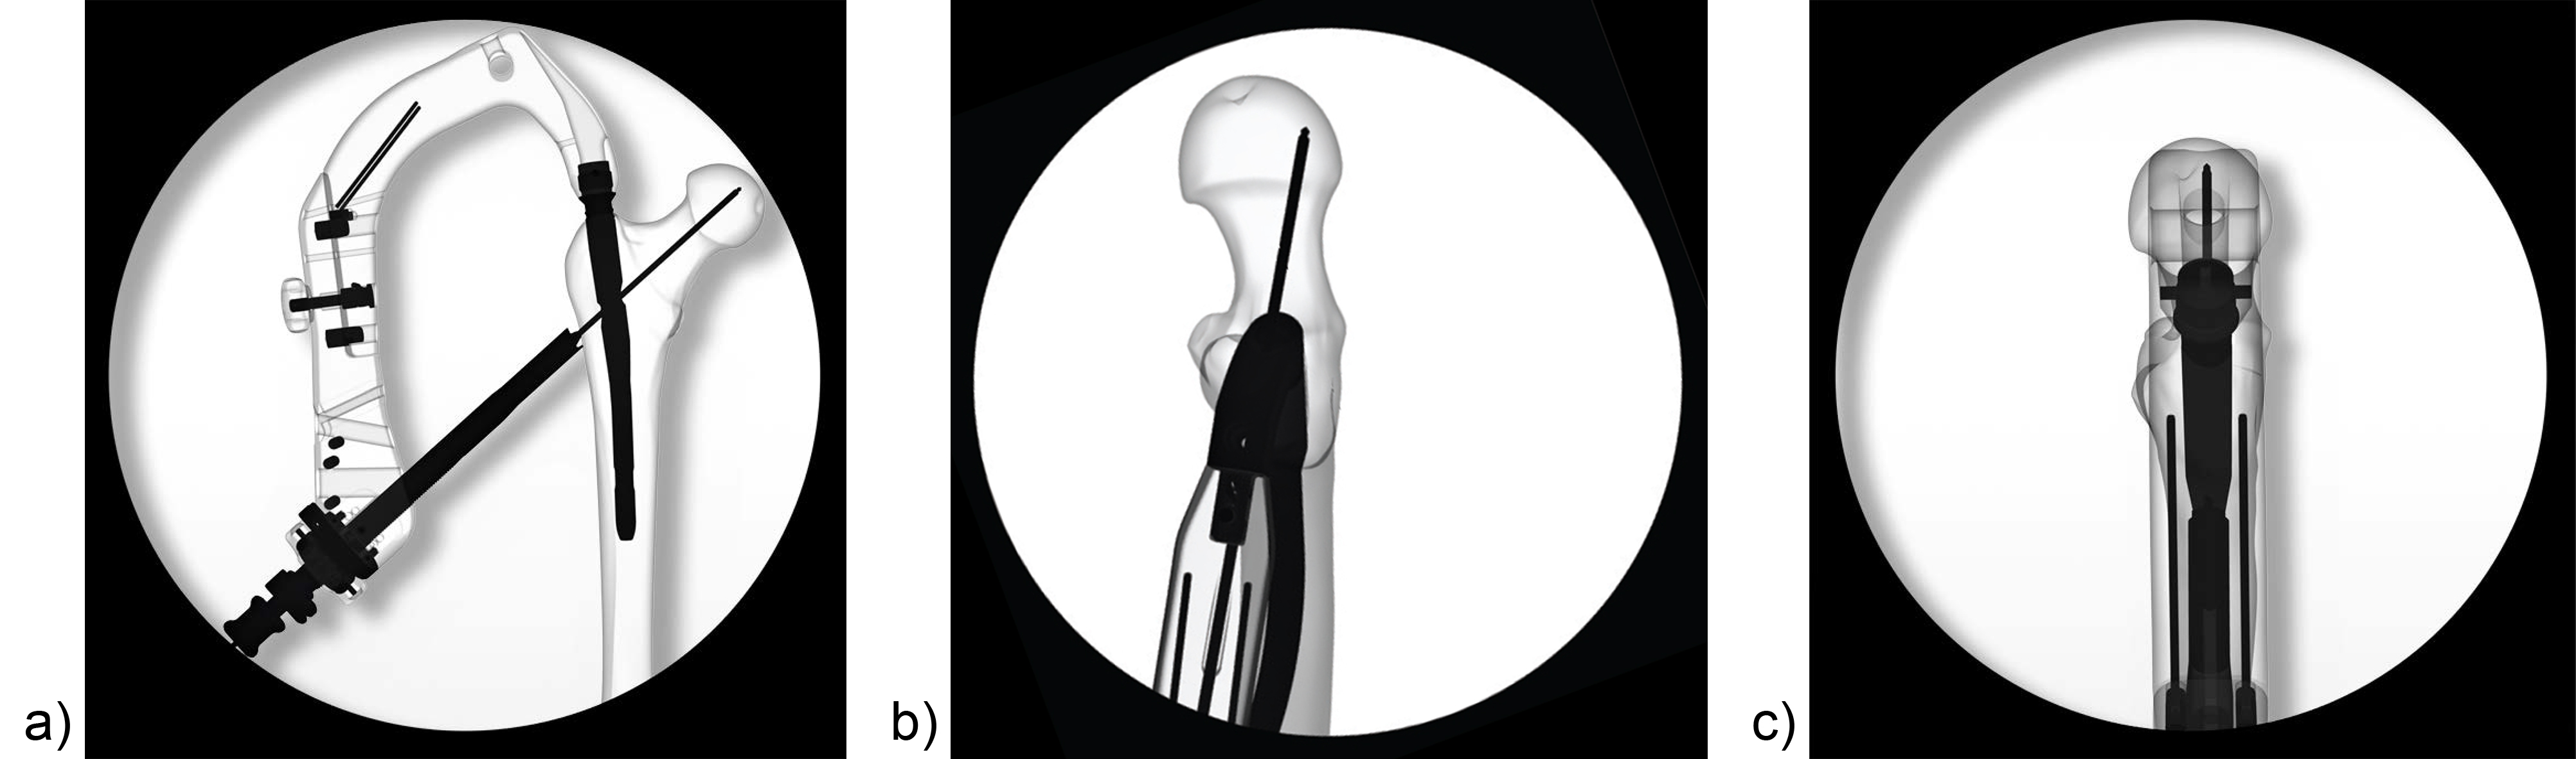

Hollow reamer

When the TFN-Advanced proximal femoral nailing system was launched in 2015, flexible and solid drill bits were offered to prepare the entry path of the nail. When fracture lines are located in the area of the intended nail insertion point, fracture fragments can be pushed apart when introducing these drill bits through the fracture lines causing a varus malreduction of the head-neck fragment. In order to avoid this clinical problem, an optional hollow reamer has been developed (Fig 5).

When using the hollow reamer, fracture fragments are not displaced because the instrument facilitates the removal of a cylindrical bone plug from the insertion area (Fig 6) without causing radial displacement forces to the surrounding bone.